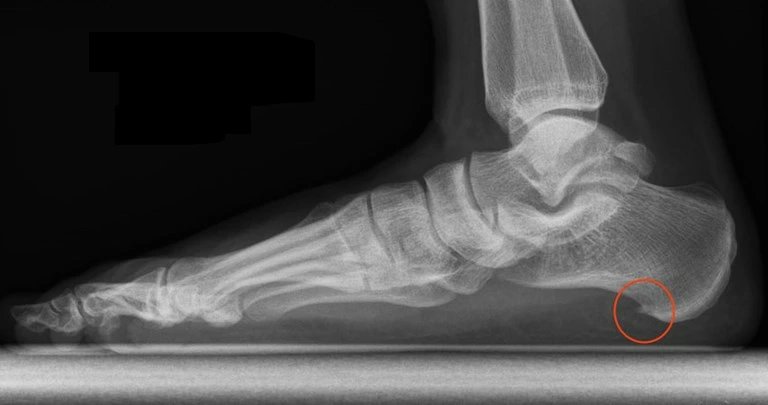

발바닥에 뼈가 튀어 나왔다던가 비정상적인 아치 형태의 경우 이에 맞는 시술(수술)이나 맞춤형 깔창이 필요할 수도 있으며 임신 등의 호르몬 변화나 갑작스러운 몸무게 증가의 경우 족부 전문 정형외과에서 적절한 치료를 받으실 필요가 있습니다.